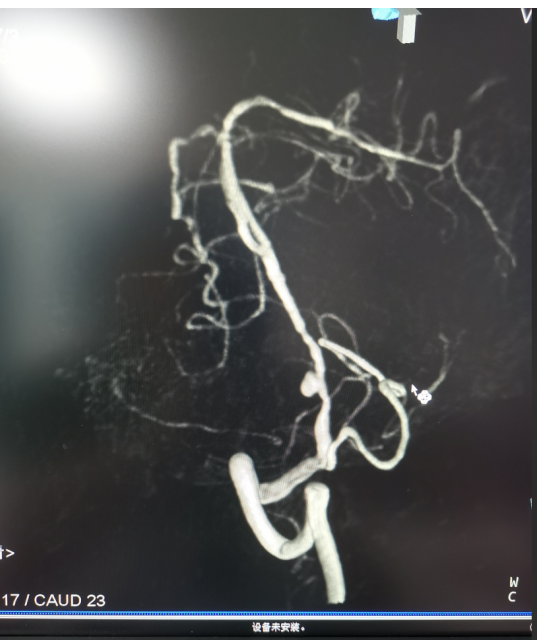

经过头部dsa检查,诊断张先生的椎动脉V4段动脉瘤为夹层动脉瘤。

神经外科团队经过深入分析和讨论,认为采用目前最先进的血管导向密网支架植入术是最佳治疗方案。相较于传统手术,这种新型手术具有更高的安全性和简便性,尤其适合复杂、难治性动脉瘤的治疗。经与患者和家属充分沟通交流,同意实施手术。

经神经外科团队与手术室、放射科、介入治疗中心等多学科紧密合作及省医院程美雄专家教授的悉心指导下,手术顺利完成。